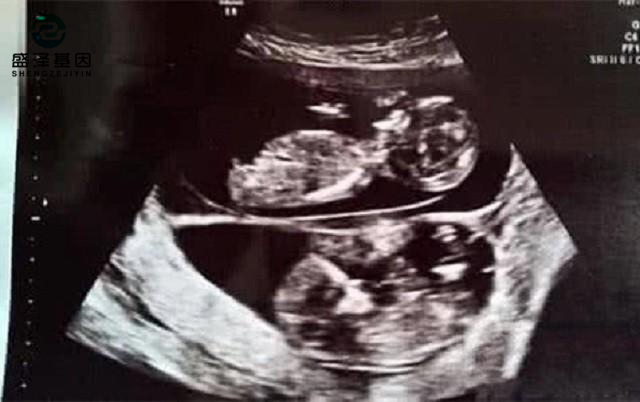

當妻子的肚子漸漸大了,阿杰帶妻子去做B超的時候,得到了一個更加令他欣喜若狂的消息:妻子懷的是雙胞胎!

不過,有些雙胞胎確實會長得不一樣。因為雙胞胎的淺層含義,就是一胎有兩個胎兒。通常情況會分同卵雙胞胎和異卵雙胞胎。

同卵雙胞胎就是一個受精卵分化成兩個胎兒,所以他們的長相幾乎一模一樣,只是會有細微的、不易察覺的區別。

而異卵雙胞胎則是母親的兩個卵子同時和父親的兩個精子結合成受精卵。同一胎會有不同長相、不同性別的顯著性狀出現。